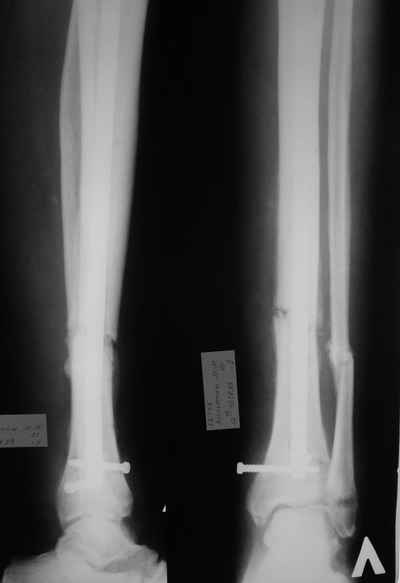

Итак - удалили стержень, воспалительный процесс к тому моменту купирован, наложили кастовую повязку и в течение 3 месяцев на контрольных рентгенограммах - признаки консолидации. Уже в сентябре, т.е черз 5 месяцев после нагноения пациент вернувшиь с подвождной охоты привез здорового сазана - основная жалоба - ноги побаливают после длительного лпаваня в ластах. Прилагаю снимки через год после удаления стержня. Вот такая, на этот раз счастливая казуистика.